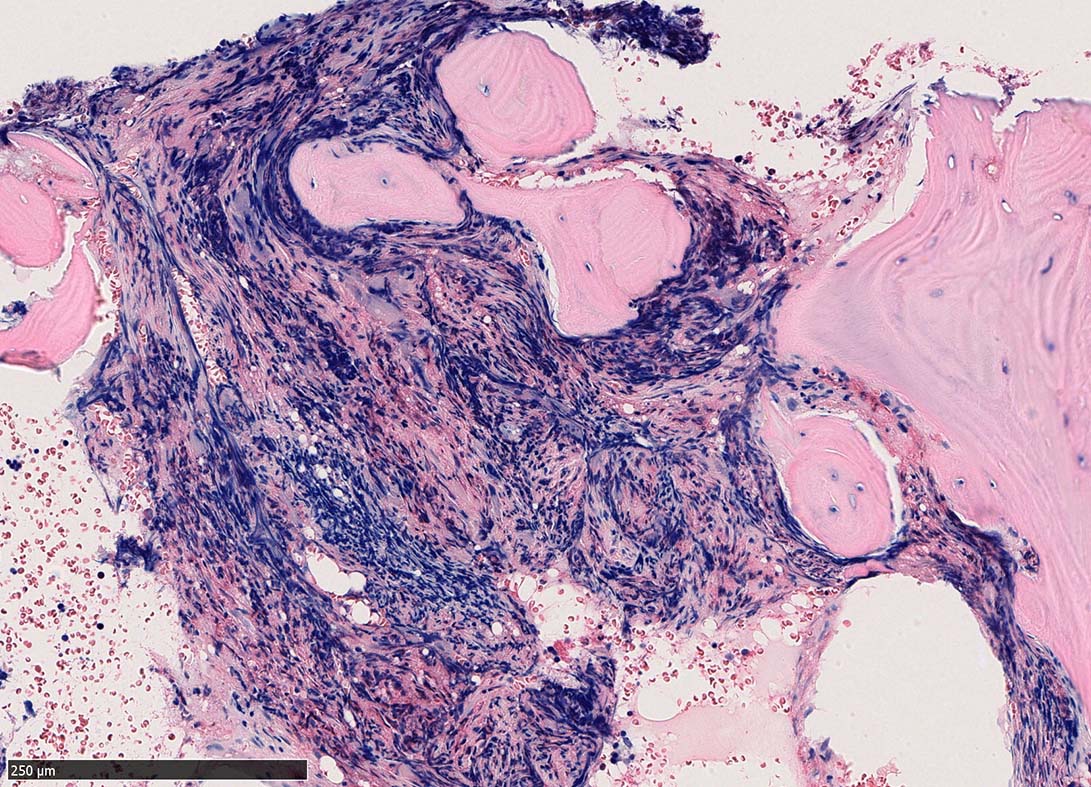

骨髄組織所見 bone marrow biopsy total 6mm in length

塗銀染色

黒染する弾性線維の増生のほか, 赤く染まる膠原線維の増生が確認される. MF-2 fibrosis. 鍍銀染色の核染色をすると膠原線維の赤染がわからなくなるので行わない.